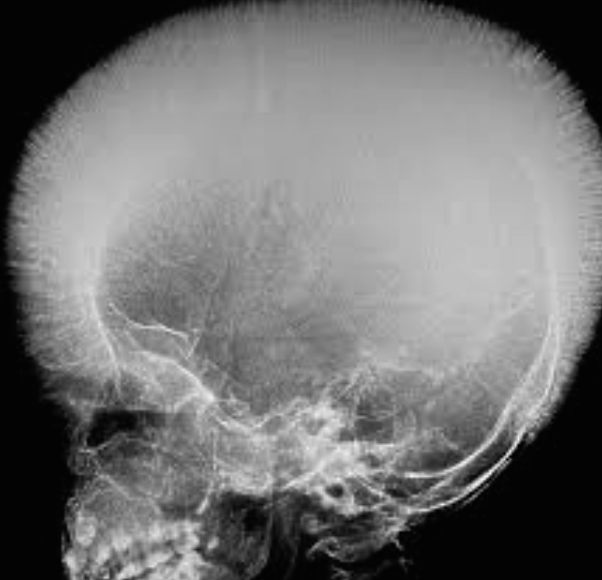

zygomatic, frontal, parietal bossing due overactivation of hemolysis

Hair on end apperance on x-ray